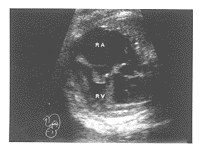

先心病组TR均有心内结构异常。其中:肺动脉狭窄3例,表现肺动脉瓣环或内径缩小,右房显著扩大,右室壁肥厚(图1)。左心发育不良综合征2例,表现左心房、室缩小,主动脉缩小,右心房、室及三尖瓣环扩大(图2)。完全型心内膜垫缺损1例,表现房间隔及室间隔上部缺失,心腔相互交通,房室瓣发育异常,形成左右心室共同房室瓣(图3)。

四腔观:右房扩大,右室肥厚

图1 肺动脉狭窄